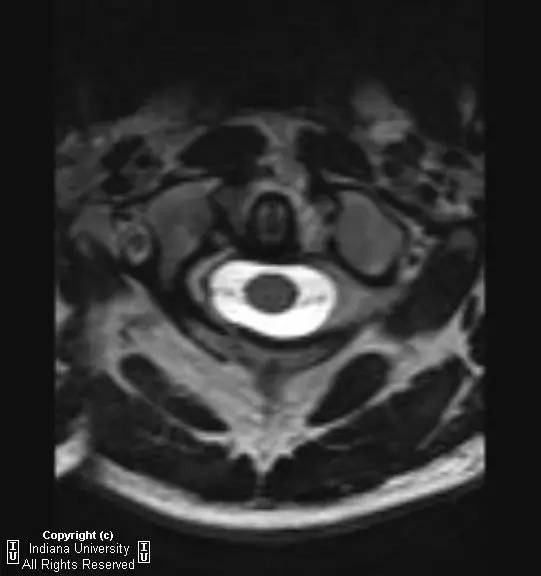

CR: C1侧块相对C2侧块外侧移位约5 – 6 mm,符合Jefferson骨折。椎体周围软组织明显肿胀。MR: 椎体周围间隙可见血肿。覆膜完整。寰枕前韧带断裂。寰枢前韧带完整。左侧横韧带从C1侧块的内侧分离,CT对应在C1侧块内侧见小撕脱骨折。翼状韧带完整。寰枕后韧带完整。前纵韧带和后纵韧带完整。黄韧带完整。

【诊断】Jefferson骨折(C1椎弓压缩骨折)

Jefferson骨折(Jefferson fracture)是前后弓均累及的C1环粉碎性骨折。Jefferson骨折为头顶受打击并轴向载荷的结果,力从颅骨经枕骨髁传递到颈椎,C1侧块在枕骨髁和C2上关节面之间被压缩,基于侧块的形状产生向心力而导致C1爆裂骨折。齿状突开口位或冠状位重建CT图像应仔细观察双侧C1和C2关节侧块间有无偏移。虽然C1侧块相对C2上关节面侧方移位提示存在骨折,但在X线片上有时难以发现骨折线。MR可显示相应的韧带损伤。

警告:C1异常时单侧或双侧寰枢椎侧方偏移可达2 mm,而Jefferson骨折通常偏移3 mm或以上。